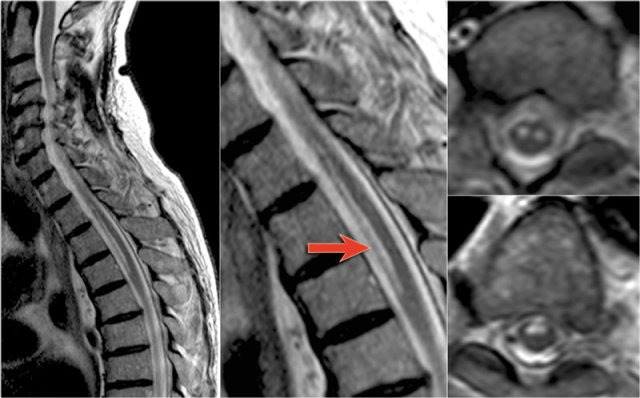

The sagittal image shows a large segment of hyperintensity on T2WI.

The transverse image shows that most of the cord is involved.

These images are of a 31 year old male with headache, voiding disturbances, urinary retention, sensory level C3.

The CSF analysis revealed 400/3 cells (meaning no infection) and a slightly higher protein level.

The images show a long segment myelopathy with full transverse involvement.

There is no swelling and no enhancement.

It does not look like MS or tumor, so we are thinking ATM - acute transverse myelitis.

Here images of a typical case of TM.

There is multisegment high signal on STIR and T2WI with some swelling.

Most of the cord in the transverse diameter is involved.

There is no enhancement, which is usually the case in TM.

Sometimes there is some patchy enhancement.

When there is enhancement, it can be difficult to differentiate TM from an astrocytoma.

On the left images of a 60 year old male with an astrocytoma.

He presented with pain in the thoracic region and sensory disturbances in the left lower extremity followed by left hemiparesis.

There is multisegment high signal on T2WI with some swelling, just like we have seen in cases of TM.

On CE-T1WI there is a region of enhancement.

The region of enhancement is more tumor-like, but the differentiation is difficult.